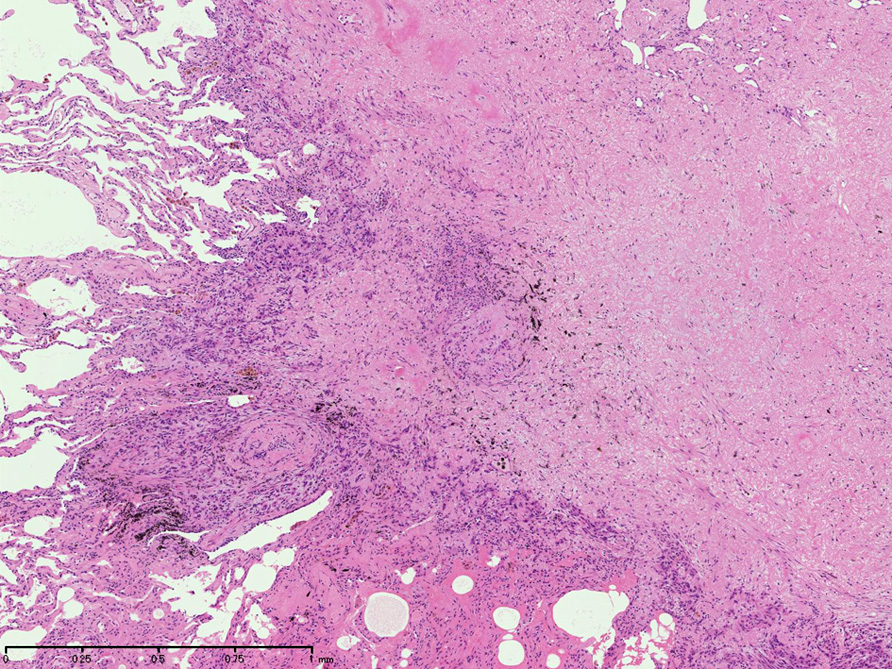

直径5-6mmの, 中央に弾性線維をふくむfibrous noduleがあり, 腫瘍細胞は結節の辺縁部に沿って認められる。

クリックすると大きな画像が見られます。